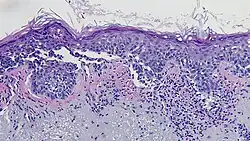

Histopathologic types

Melanoma is a type of neuroectodermal neoplasm.[85] There are four main types of melanoma:[86]

SN Type Features Incidence[86][notes 1] Photograph Micrograph

1. Superficial spreading melanoma Melanoma cells with nest formation along the dermo-epidermal junction. 70%

2. Nodular melanoma Grows relatively more in depth than in width. 15% - 20%

3. Lentigo maligna melanoma Linear spread of atypical epidermal melanocytes as well as invasion into the dermis.[87] 5% - 10%

4. Acral lentiginous melanoma Continuous proliferation of atypical melanocytes at the dermoepidermal junction.[88] 7% - 10%